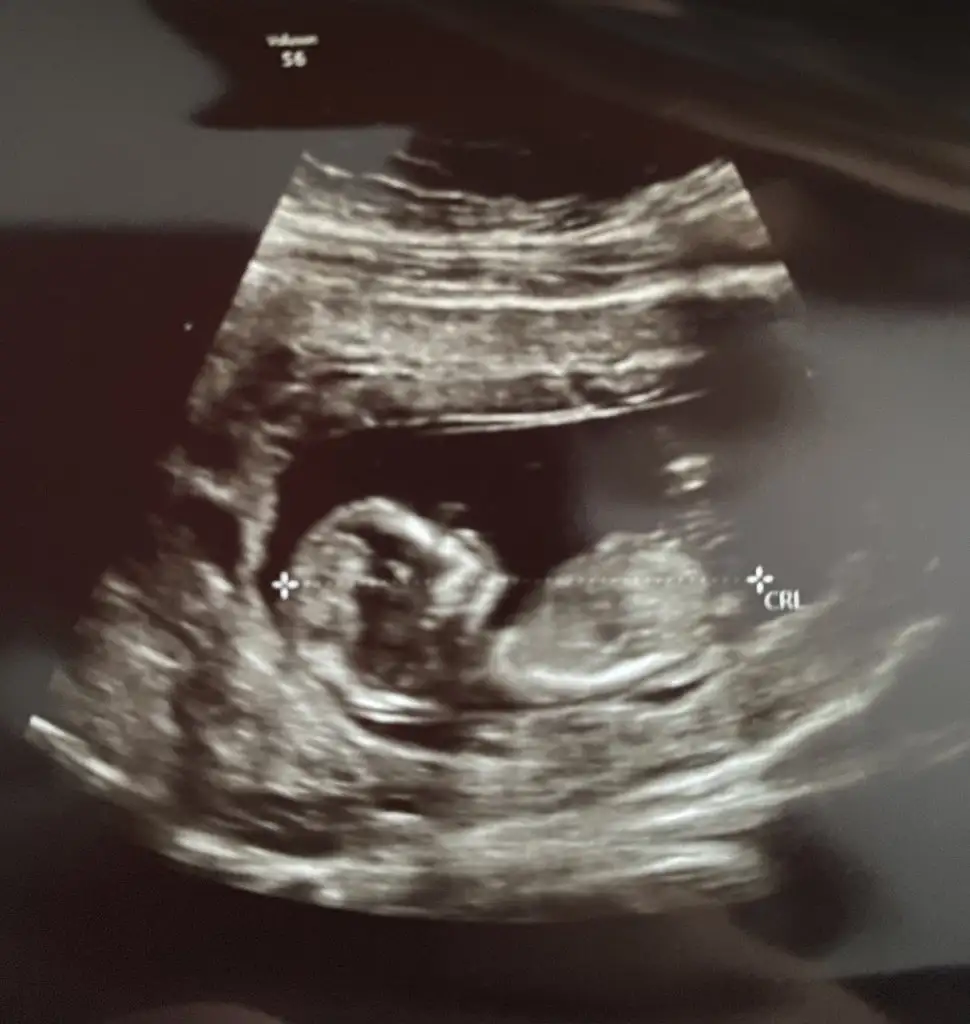

12+6 yorumlarmısınız lütfennŞimdiden teşekkürler

Eklentiler